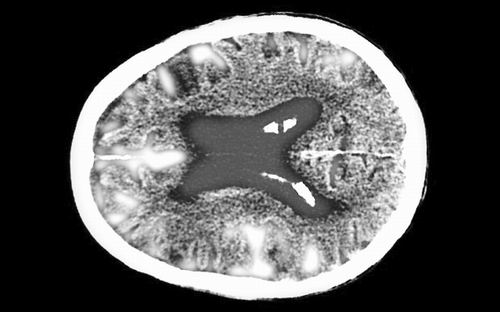

脑部CT扫描轴向剖面显示出一位84岁的男性阿尔茨海默病患者脑部的萎缩情况。图片来源:ALAMY